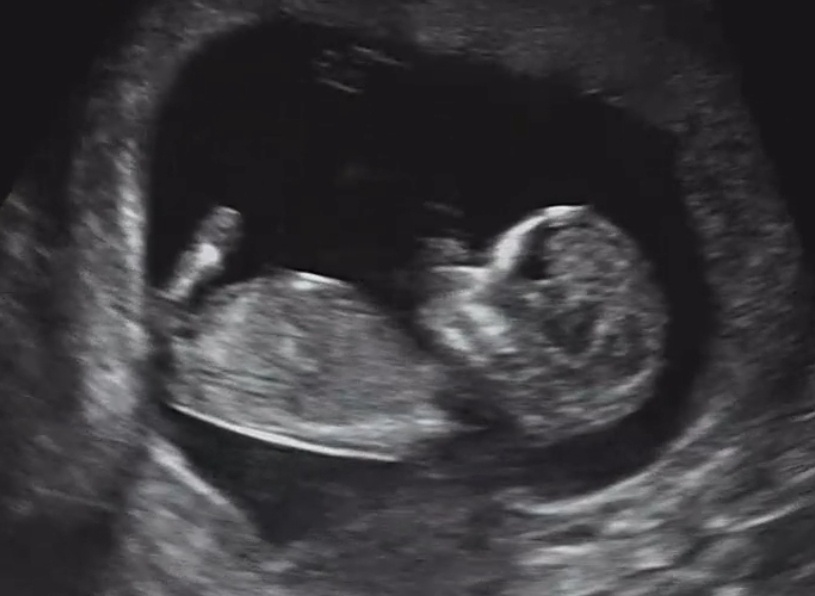

초음파로 처음 사람다운 형태를 확인했을 때 그는 겨우 4.71cm였다. 4.71cm. 키위보다도 작은 그 안에 팔과 다리와 눈, 코, 입이 모두 자리를 잡고 있었다. 그랬던 아이가 지금은 한 손에 키위를 움켜쥘 만큼 자라 있다. 요즘 선이는 자연관찰책을 꺼내 와 내게 읽어달라고 한다. 우리는 함께 바닥에 엎드려 얼굴을 맞대고 책 속으로 빠져든다. 무당벌레는 낙엽 밑에서 겨울잠을 자고 바구미는 도토리 속에 알을 낳는다고 한다. 읽어주는 나도, 자세를 바꿔가며 집중하는 선이도 모두 자연의 신비에 감탄한다.